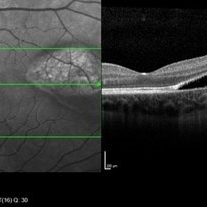

Coupled OCT B-scan and IR imaging of an asymptomatic 12-year-old girl with torpedo maculopathy of the left eye. One can see that there is no involvement of the fovea which explain that the patient has no visual sign.

Photographer: Pierre-Henry Gabrielle, Ophthalmology department, Dijon University Hospital, France

Imaging device: Heidelberg Spectralis

Condition/keywords: optical coherence tomography (OCT), torpedo maculopathy